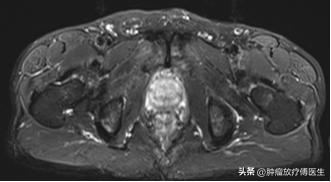

2015年10月29日我院泌尿外科行经尿道前列腺电切术,术后病理示前列腺腺泡腺癌,Gleason评分5+4=9。术后恢复可,期间出现全身酸痛,2015年11月17日查骨ECT示全身多发骨(颅骨、脊柱、骨盆、双侧肋骨、胸骨、双侧肩胛骨、左侧肱骨、双侧股骨)放射性异常浓聚。2015年11月27日行盆腔MRI报告:前列腺外周叶及中央叶多发结节样异常信号,结合病史,考虑前列腺癌。行胸、腰椎MRI平扫+增强:胸、腰椎体、双侧髂骨及所见双侧股骨多发结节状异常信号影,考虑转移灶。

2015-11-27盆腔MRI图像